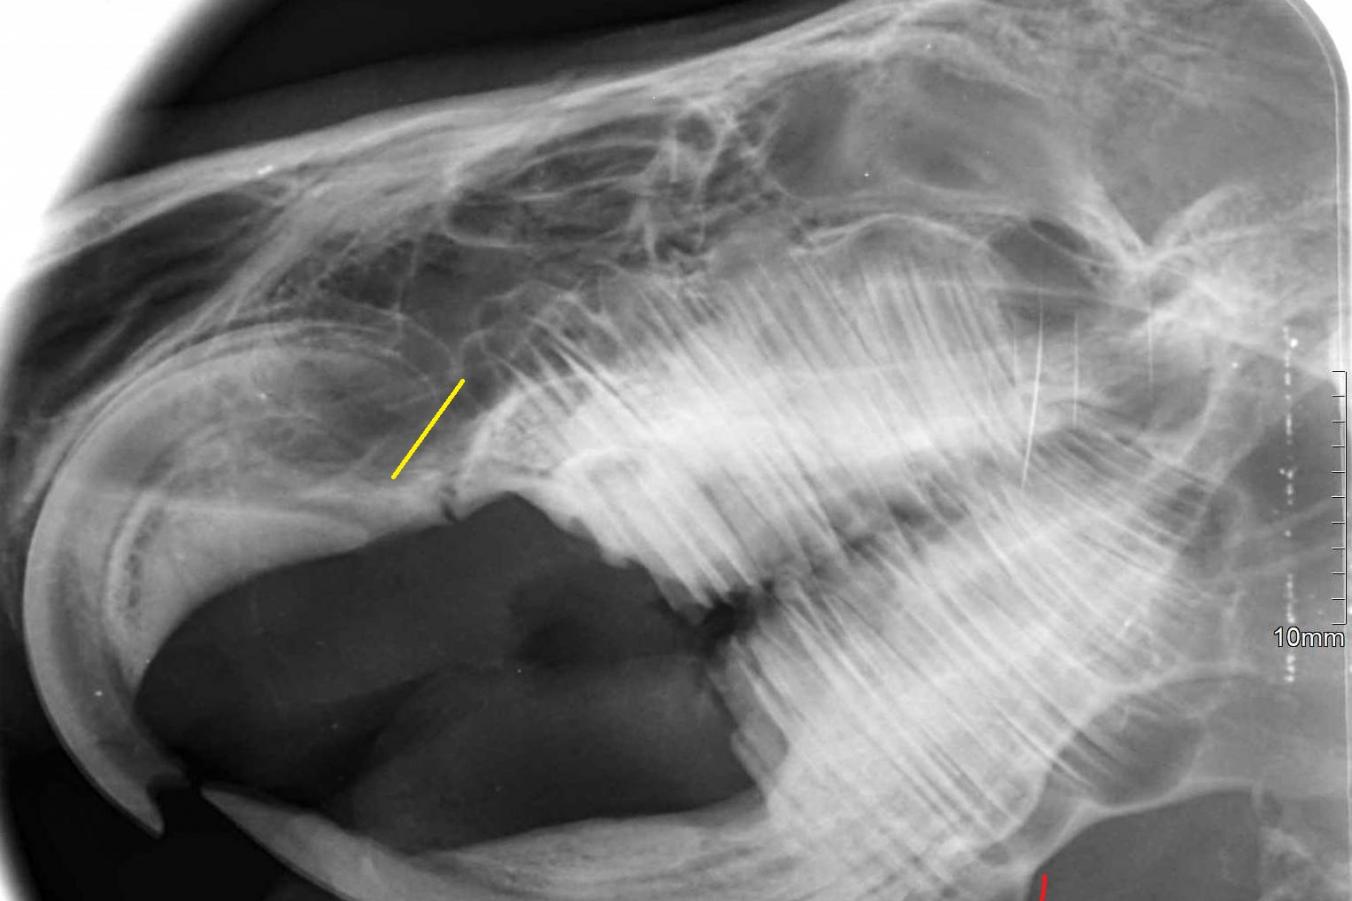

Za dvěma páry řezáků, které jsou vidět na první pohled, jsou v tlamičce schované ještě stoličky (správně premoláry a moláry) – a to čtyři na každé straně nahoře i dole. Všechny zuby morčete neustále dorůstají. Při normálním obrušování zubů vyrostou řezáky o 3 mm za týden, stoličky o 2–5 mm za měsíc. Pokud se zuby neobrušují, protože morčátko například nepřijímá potravu a je dokrmováno tekutou stravou, růst zubů se zpomaluje. Viditelná část spodních řezáků je obvykle třikrát delší, než viditelná část horních řezáků. Na bočním rentgenu vidíte, že velká část řezáků je ještě „schovaná“ v kosti. Spodní stoličky nerostou kolmo vzhůru, ale jsou nakloněny přes jazyk šikmo k sobě v úhlu asi 40°. Horní stoličky naopak míří mírně směrem ven do dásně pod tvářemi.

Žlutou barvou jsou vyznačeny konce kořenů řezáků, červenou barvou přerůstání kořenů stoliček v čelisti